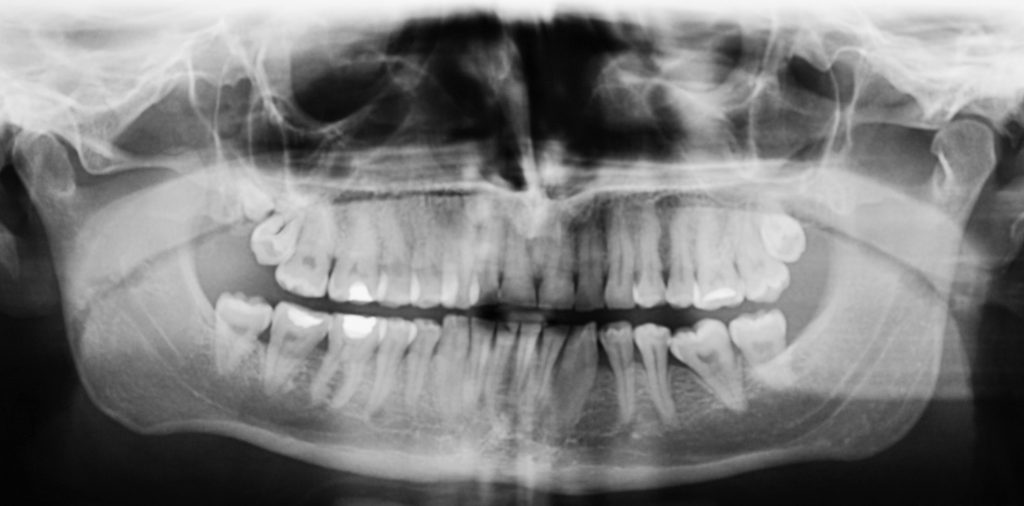

Streszczenie: W pracy przedstawiono zagadnienie występowania zębów nadliczbowych w okolicy zębów trzonowych szczęki. Opisano dwa przypadki medyczne. Przypadek pierwszy dotyczy 22-letniego pacjenta, u którego przypadkowo w badaniu radiologicznym wykryto całkowicie zatrzymany ząb zatrzonowy. Przypadek drugi opisuje ząb zatrzonowy wyrznięty nad całkowicie zatrzymanym zębem trzonowym trzecim, będący przyczyną zębopochodnego okołoszczękowego stanu zapalnego.

Summary: The paper describes the incidence of supernumerary teeth in the region of the maxillary molars. Two cases are presented. The first case is a 22-year-old male patient in whom a totally retained distomolar was found by accident in an X-ray examination. The report of the other case describes a retromolar tooth erupted above a totally retained wisdom tooth, being the cause of odontogenic infection in the jaws.